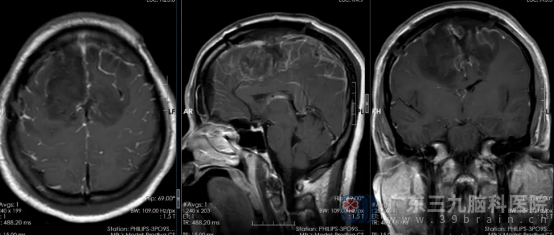

征得患者及家属同意,手术由鲁明主刀,卢建侃带领神经外五科团队辅助,成功为患者实施微创肿瘤切除术,术中在显微镜下全切肿瘤,病理确诊为良性脑膜瘤。

▲术后复查影像

术后,李女士恢复良好,未出现任何神经功能损伤,经专科治疗护理,很快就顺利出院。“幸亏发现及时!”李女士感慨道。